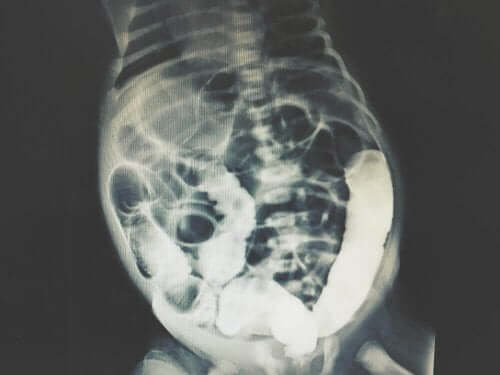

Kun tulokset on saatu, asiantuntijat pystyvät määrittämään syyn vatsan muutoksiin. Potilaan vatsa saatetaan myös kuvata diagnoosin tekemisen helpottamiseksi.